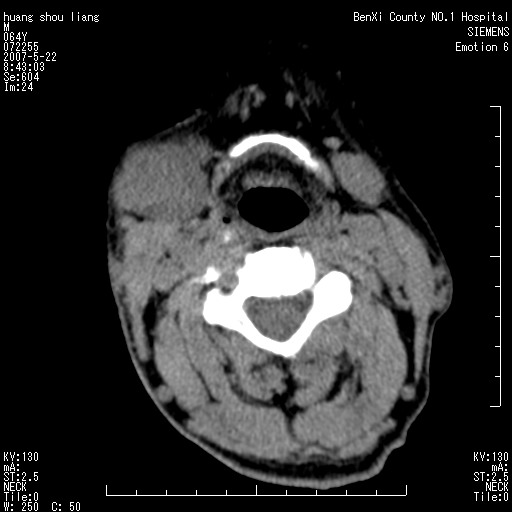

男性,64岁。颈部包块8年。最近增大。

对不起大家,可能是片子发太多有点乱,正常腮腺在下颌角的外侧,颌下腺在下颌体的中部内侧,本例在下颌角内侧偏下,和腺体一点关系都没有,从vrt和mpr上可以很明显看出来,再者肿块是好多粘连在一块的,大家在仔细看看,左侧可能也是吧,我还是考虑为肿大的淋巴结融合在一块,但性质??????

右侧腮腺下部均匀软组织密度肿块,外形不规则,与周围组织分界清晰,考虑右侧腮腺混合瘤或多形性腺瘤。

大家好,病理结果出来了,如大家所说,颌下腺混合瘤。

唉,解剖没学好吧,我诊断错了,不过还是有些不理解回去我在多看看书,谢谢大家的参与,以后我还会奉献好的病例。